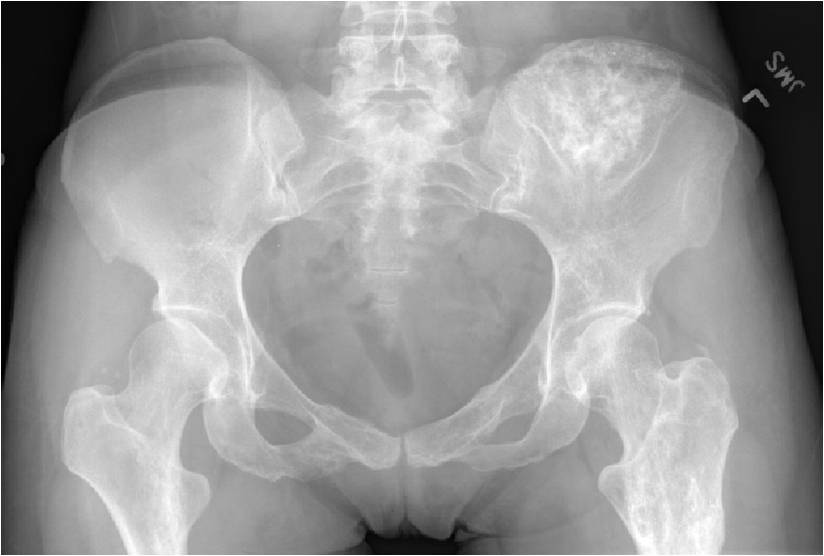

- Enchondromas of the pelvis, vertebrae and ribs are uncommon

- Almost all hyaline cartilage tumors of the pelvis are considered malignant based on anatomic location no matter what the pathology shows. These tumors will ultimately grow locally and have the potential to dedifferentiate or change into a higher grade chondrosarcoma.

- Features consistent with chondrosarcoma

- Cortical destruction and a soft tissue mass

- Periosteal reaction and thickening

- Endosteal erosion>2/3 cortical thickness on a CT scan

- Size greater than 5 cm